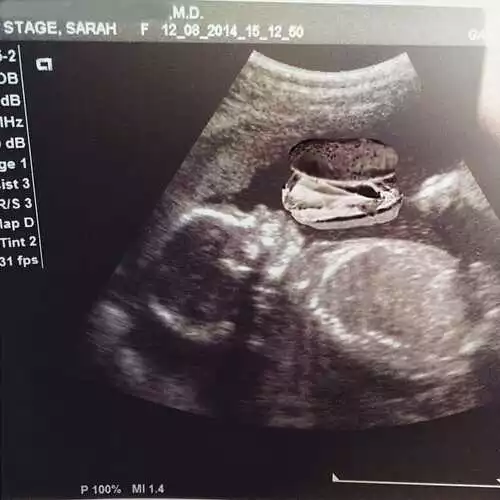

这是她宝贝的B超。医生说宝宝的各项身体指标都正常!